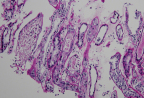

Biopsy image showing acute tubular necrosis in a kidney. (Credit: Feinstein Institutes)

Researchers published their findings July 13 in the Journal of American Society of Nephrology, describing biopsied kidney samples from 10 patients treated at Northwell Health – New York State’s largest health system and responsible for treating more hospitalized COVID-19 patients than any health system in the nation between March and May – who tested positive for COVID-19 and exhibited clinical features of AKI. The kidney biopsy samples revealed the presence of ATN, some with other pathological findings, but no evidence of the virus in the kidney tissue itself.

Since kidney injury has been observed in COVID-19 patients, the question of direct viral infection of the kidney has been debated by the medical research community. Through this research, there was no ultrastructural or immunohistochemistry evidence to show viral infection, and instead, the investigators hypothesize that the main mechanism of kidney injury is through ischemic/hypoxic (the lack of oxygen being delivered to the kidneys), or sepsis-related injury.

The paper outlines the care protocol and biopsy results on the 10 patients (five males, five females) case series. The mean age of the patients was 65 years old; five were Black, three Hispanic, and two white. All patients had proteinuria and some had hematuria. All 10 biopsies showed tubular injury of varying degrees. Eight of the patients required dialysis during their hospital stay.